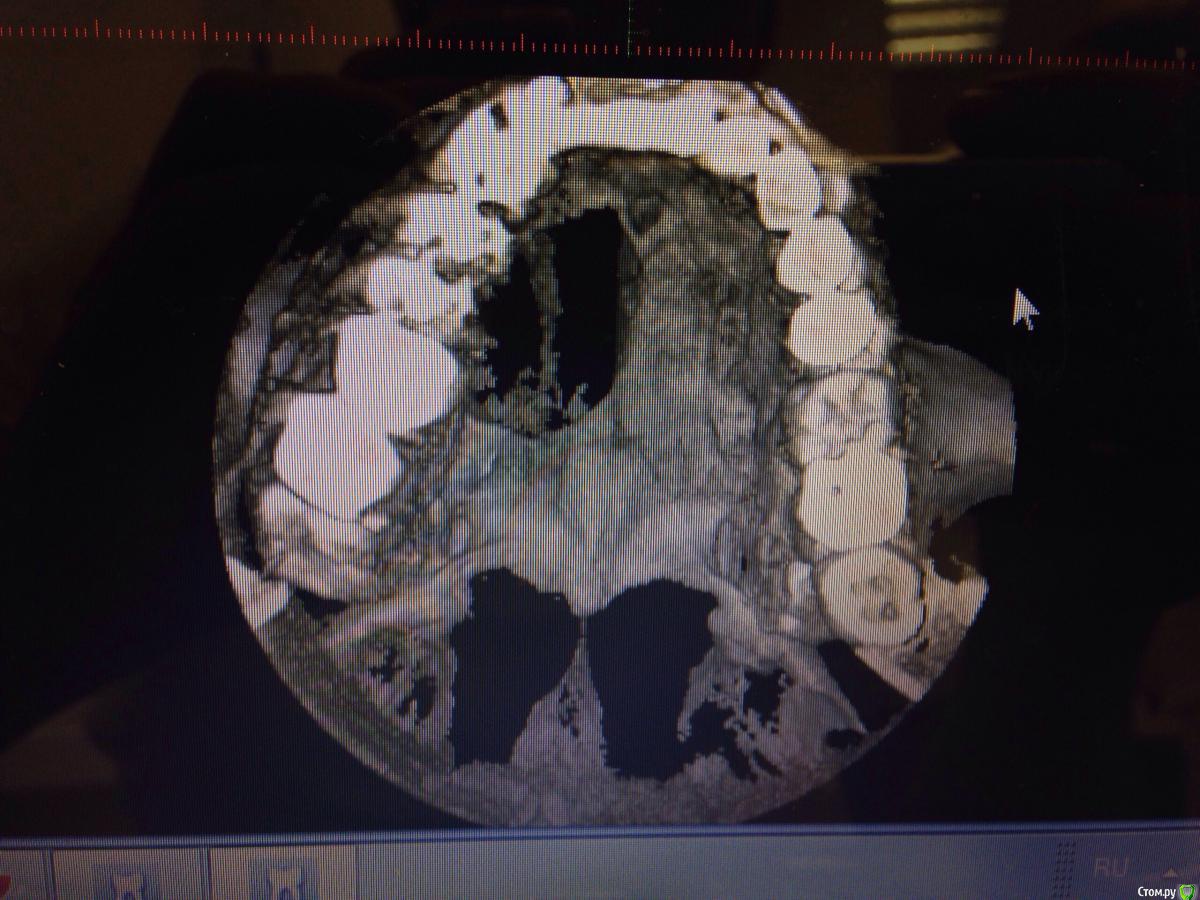

Денис481 Опубликовано 22 октября, 2015 Поделиться Опубликовано 22 октября, 2015 Пришел пациент с жалобами на боли 21,22 зуба. Зубы вылечены,но в ходе лечения обнаружен очаг воспаления,который захватывает половину неба,и выходит свищевым отверстием над 12 зубом,со слов пациента в течении 1,5 года зуб лечили 2 раза. Объективно канал обтурирован,содержимое плотное,гуттаперча,но очаг пол года не уменьшается и постоянно при нажатии выделяется гнойное содержимое Ссылка на комментарий

Денис481 Опубликовано 22 октября, 2015 Автор Поделиться Опубликовано 22 октября, 2015 После пациент направлен на консультацию в члх,затем поступил с направлением вылечить каналы 11-14 зуба,что собственно и сделано Ссылка на комментарий

Денис481 Опубликовано 22 октября, 2015 Автор Поделиться Опубликовано 22 октября, 2015 Вопрос,лечить консервативно,или все таки операция? Ссылка на комментарий